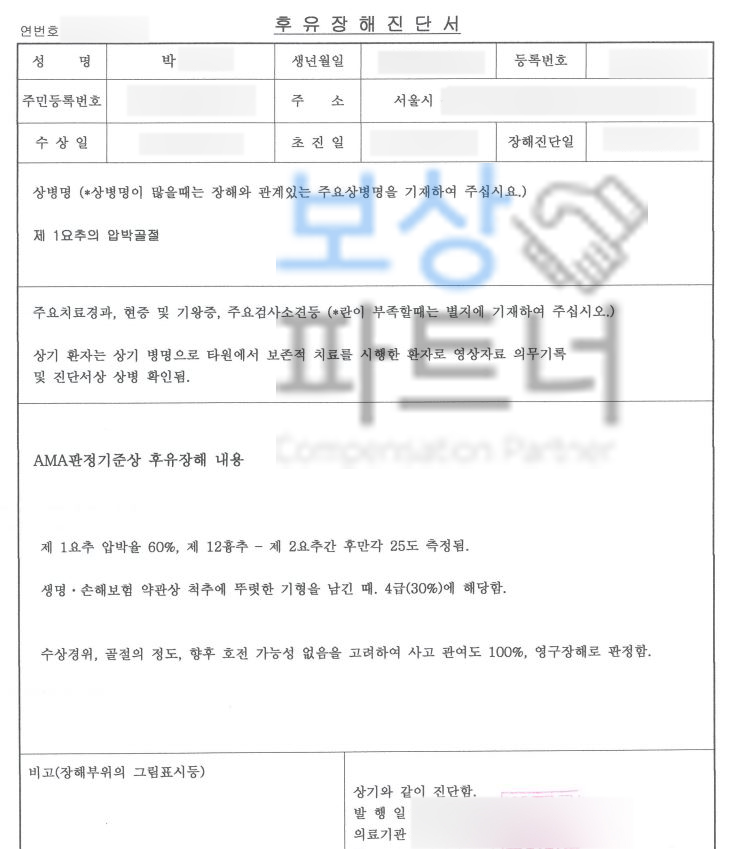

의료 전문의의 후유장해진단서

필수 서류입니다. 하지만 치료받은 병원의 주치의는 자신의 치료에 장해 판정을 하기 쉽지않고 일반 보험소비자가 대학병원에 가서 장해평가 받기도 쉽지 않은 것이 현실입니다. 요추압박골절 1번척추 허리뼈골절 비수술 30% 4급 장해 보상

또한 장해진단서를 발급받아 보험사에 청구한다 해도 보험사의 조사관은 여러 이유들로 보험금 삭감을 진행합니다. 위와 같은 상황이 우려되었던 박@@님은 보상파트너의 도움을 받아 보험금 청구를 진행하셨는데요, 먼저 보험증권과 영상CD, 의무기록 받아 보상 전략과 가능성을 확인하였습니다.

영상CD 및 영상판독지를 보면 Acute compression fracture in L1 **급성 요추압박골절 **확인됩니다. 보상파트너는 보험사도 인정할 공신력있는 상급병원 전문의로부터 후유장해 평가 받았고

박@@님의 보험금 청구 도와드렸습니다. 요추압박골절 1번척추 허리뼈골절 비수술 30% 4급 장해 보상 보험사와 약 2달간의 첨예한 분쟁이 오갔습니다.

하지만 박@@님은 보상파트너와 함께해

후유장해 보험금 35,400,000원

지급받을 수 있었습니다. 요추압박골절 장해 보상 치료도 보상도 해당 전문가에게 문의하세요. 보상파트너의 모든 상담은 무료로 진행됩니다.